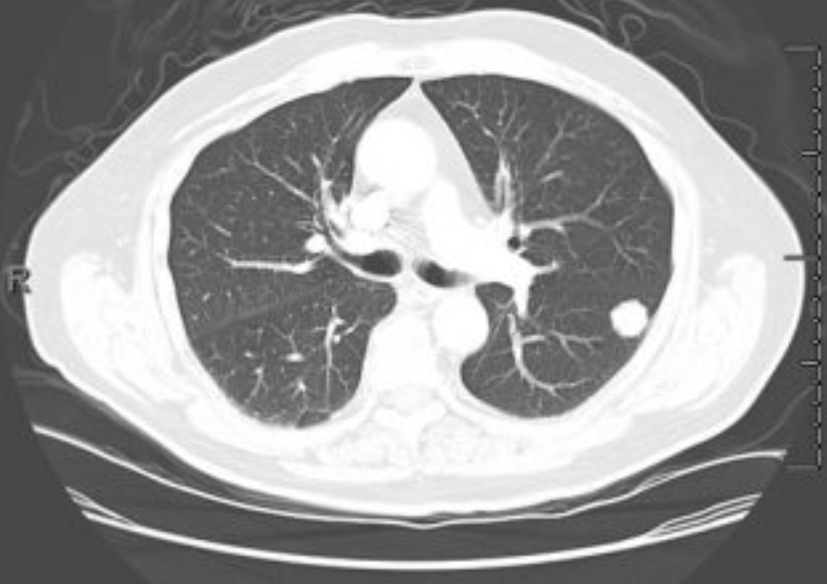

폐암은 초기에 특별한 증상이 거의 없어서 조기 발견이 어렵습니다. 흉부 엑스레이는 폐암을 찾아내는 첫 번째 단계로 사용돼요. 작은 혹이나 결절이 보이면 추가로 저선량 CT(방사선량이 적은 컴퓨터 단층촬영)를 진행하게 되죠.

하지만 엑스레이만으로 모든 폐암을 잡아내긴 어려워요. 종양이 아주 작거나 혈관 뒤쪽에 숨어 있으면 안 보일 수도 있습니다. 그래서 흡연력이 있거나 가족력이 있는 분들은 1년에 한 번 정도 저선량 CT를 병행하는 게 좋아요. 저희 아버지도 금연 후 매년 CT를 찍고 계신데, “한 번 찍으면 마음이 편하다” 하시더라고요. 그 말이 참 와닿았어요. 예방이 곧 안심이니까요.